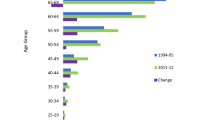

Incidence rates by calendar period and birth cohorts

Assuming a period slope of zero and hence drift attributed entirely to birth cohort, Fig. 7 presents for the USA and UK by sex the fitted longitudinal age-specific incidence rates (based on the reference cohort 1945) and relative changes (rate ratios) in incidence of OS, ES, and CS among cohorts born before and after the cohort reference. The sex-specific cohort effects conveyed some similarities in the UK and USA: A decrease in OS is evident in both sexes in the UK and among US men in cohorts born from 1890 to 1925, with minor increases thereafter. The CS incidence rate ratio increased in successive cohorts born during 1925–1955 in US females as well as in both sexes in the UK. For ES, an increase followed by a leveling off or decrease (in US women) in the rate ratios was observed in successive generations in both US and UK men and women, though caution is needed given the relatively few cases involved.